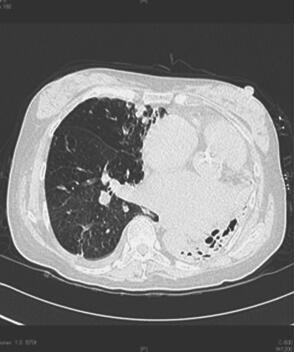

辅助检查:血常规:WBC 7.98×109/L,Hb 130g/L,PLT 173×109/L,N 75.4%。凝血:PT 14.6秒,APTT 28.7秒,Fbg 2.75mg/dl,D-二聚体364μg/L。胸片见图1,胸部CTA见图2。超声心动图示心房增大,肺动脉高压,PASP 51mmHg,主动脉硬化、瓣膜钙化并狭窄及反流,三尖瓣中重度关闭不全、左心室收缩功能正常。腹部B超示肝静脉及下腔静脉增宽,注意排除右心功能不全可能;门静脉主干增宽,未见血栓;肝周少量积液。

图2 4月7日胸部CTA示左侧毁损肺并肺动脉高压,右肺中叶纤维增殖钙化性结核灶,右肺炎症